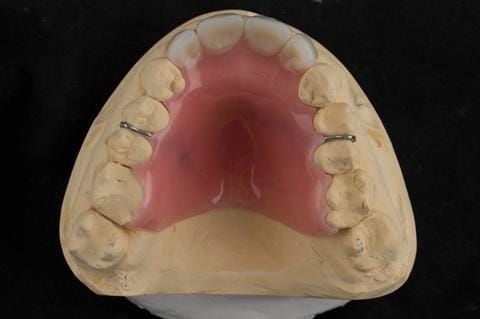

- Extract the upper 2-2 teeth and replace with an interim acrylic based partial denture. Reline the interim denture over 9 - 12 months, replacing with a definitive cobalt chromium based partial denture. The definitive denture would ideally be designed as an occlusal protective splint to reduce the the potential for mechanical wear and breakages of the moderately/heavily restored maxillary dentition. In addition, should further upper teeth require extraction they could be added on to the denture cobalt chromium framework - therefore a new prosthesis would not be required as future teeth are lost. This option would produce an excellent aesthetic outcome. This is the option the patient chose to have.

Following consultation and second discussion appointment the patient chose to have option 3 namely, a maxillary cobalt chromium based partial denture/protective occlusal splint. The clinical situation and treatment process is shown in detail below with photographs. The patient was successfully rehabilitated with this and her quality of life considerably improved. The clinical work was provided by Finlay and the technical work by Rowan.